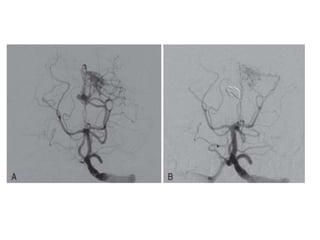

TRATAMIENTO ENDOVASCULAR

EMBOLIZACION DEL

ANEURISMA: COILS

TRATAMIENTO

DEFINITIVO

TRATAMIENTO QUIRURGICO

• LA HSA NO SE OPERA

• HEMORRAGIA INTRACEREBRAL SI SE OPERA

• CLIPAJE DE ANEURISMA: EVITA RESANGRADO,

PERMITE MANEJAR ALTOS VOLUMENES Y PA

HUNT Y HESS I , II Y III.